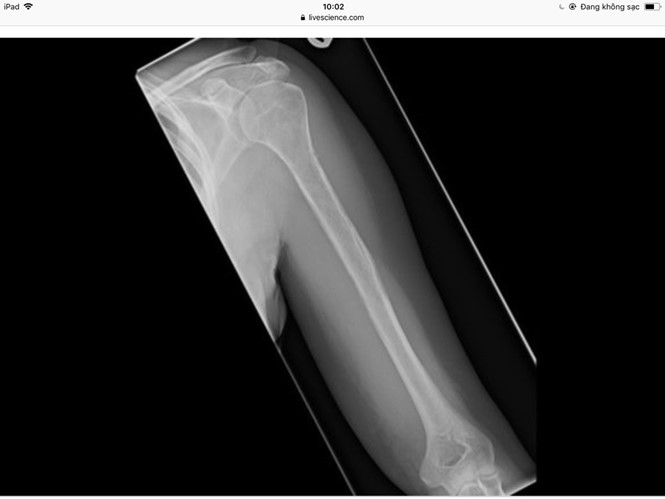

Old  Default Căn bệnh mất xương cực hiếm

Một phụ nữ 44 tuổi (giấu danh tính) luôn thấy đau ở phần bắp tay và vai, đã đi khám nhiều nơi nhưng các bác sĩ vẫn không lý giải nổi những triệu chứng này.

Một bác sĩ đã quyết định chụp X-quang cho bệnh nhân. Kết quả cũng rất kỳ lạ khi xương của bệnh nhân dường như mất đi trước mắt của các bác sĩ, theo Live Science ngày 3.4.

Ngoài ra, các bác sĩ cũng cho bệnh nhân làm các sinh thiết thêm. Kết quả cho thấy những mạch máu phát triển thay thế vị trí xương biến mất.

Dựa vào hiện tượng đặc biệt này, các bác sĩ của Bệnh viện Hoàng gia Edinburgh (Scotland) đã chẩn đoán bệnh nhân bị bệnh Gorham-Stout. Đây là một căn bệnh cực kỳ hiếm làm cho người bệnh bị mất xương.

Đến bây giờ, nguyên nhân gây nên căn bệnh này vẫn còn là điều bí ẩn mà các bác sĩ và nhà khoa học chưa tìm ra được.

Họ chỉ biết rằng bệnh nhân mắc bệnh Gorham-Stout này có những mạch máu và mạch bạch huyết phát triển không bình thường, làm cho xương gãy và biến mất. Sau đó, những khối u trên mạch máu thay thế vào những xương đã bị biến mất này, theo Tổ chức Quốc gia về Các bệnh Hiếm (Mỹ).